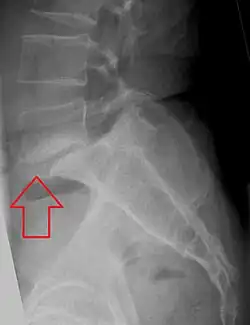

Espondilolistese na vértebra lombar L5.

Espondilolistese é o deslocamento anterior de uma vértebra ou da coluna vertebral em relação à vertebra inferior[1][2], ou, mais geralmente, em qualquer direção. [3][4]